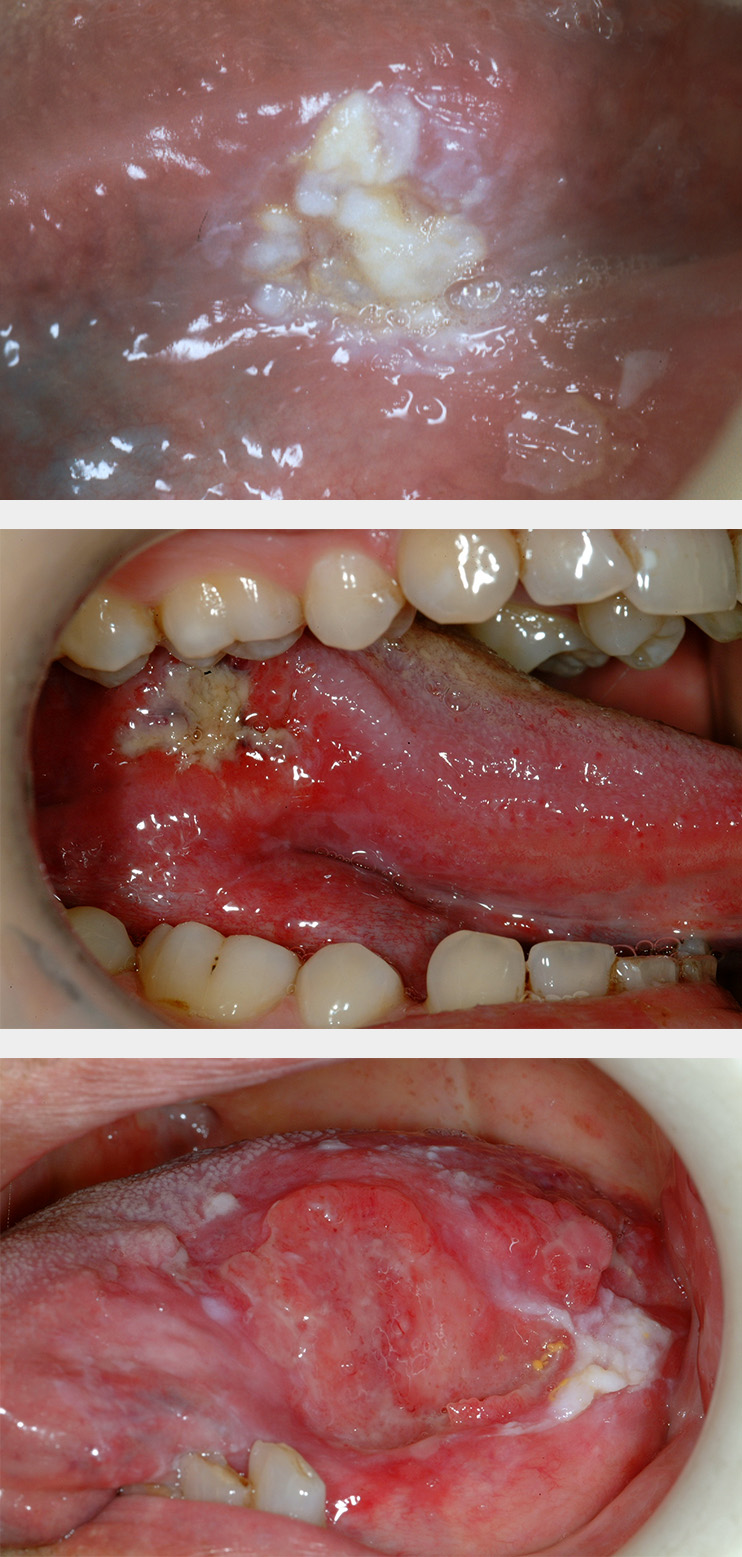

Leukoplakia

Oral leukoplakia (according to the World Health Organisation definition) is a white patch or plaque that cannot be characterised, clinically or histopathologically, as any other disease. There are a number of possible causes for white patch oral mucosal lesions and similar looking such lesions are quite common. Leukoplakic patches can appear in all areas of the mouth but the side of the tongue and the floor of the mouth (see Figure 1) are common locations. Leukoplakic patches come in a range of appearances and may be completely asymptomatic or cause symptoms. The overall risk for leukoplakic patches to become malignant has been quoted as 2 to 8 %.

Erythroplakia

Erythroplakia is defined as a red patch (see Figure 2) that cannot be diagnosed as any other lesion. Erythroplakia is less common than leukoplakia but tends to display more severe degrees of dysplasia as well as a higher overall risk of malignant transformation; the overall risk has been quoted as 14 to 67 % (see below), and approximately 40 to 50 % of erythroplakic patches have high-grade dysplasia or carcinoma in situ present. The most common sites for erythroplakia are the floor of the mouth, tongue and soft palate.

Erythroleukoplakia

Erythroleukoplakia (also known as speckled leukoplakia) is the third of the oral mucosal lesions commonly associated with a risk of malignant transformation (see Figure 3). Speckled leukoplakia is an intermediate risk for malignant transformation.